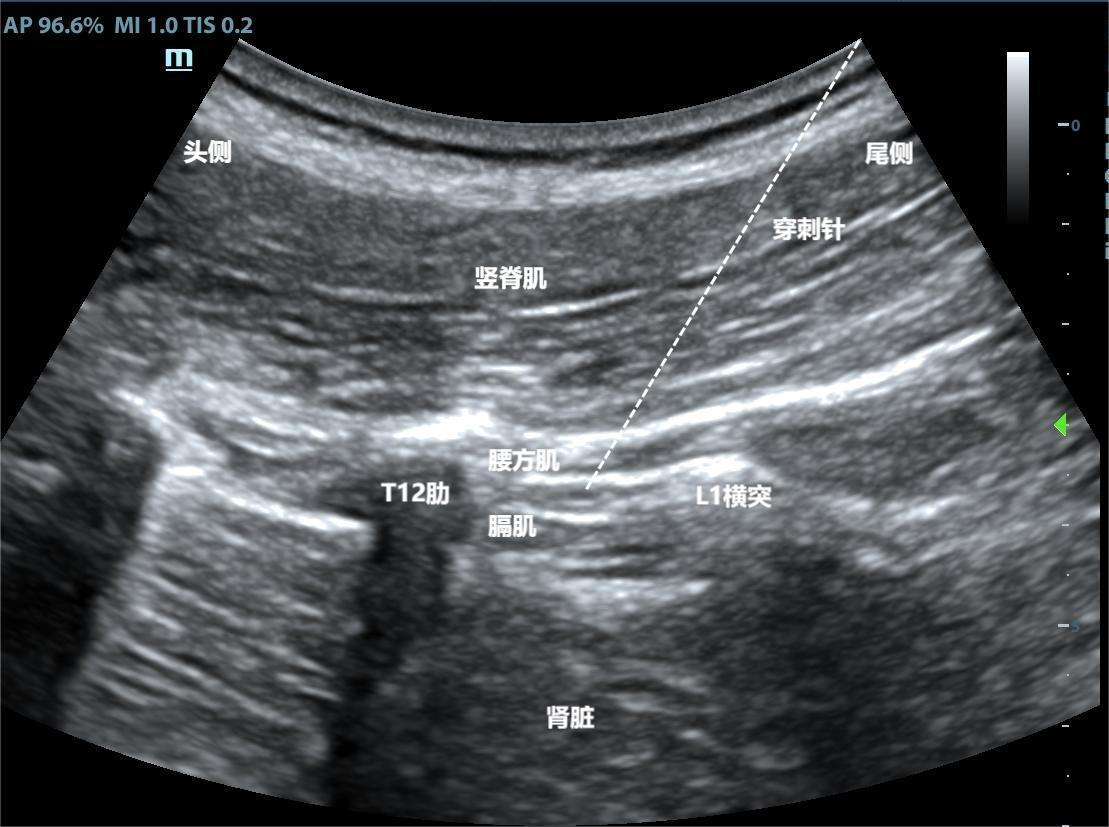

目的 探讨超声引导下弓状韧带上腰方肌阻滞对机器人辅助腹腔镜前列腺癌根治术老年患者术后镇痛及炎症反应的影响。 方法 选择2022年6月至2023年6月择期行机器人辅助腹腔镜前列腺癌根治术老年患者60例,随机分为超声引导弓状韧带上腰方肌阻滞联合全麻组(观察组,n = 30)和单纯全麻组(对照组,n = 30),两组患者术后均使用静脉自控镇痛。记录镇痛泵首次按压时间、有效按压次数及补救镇痛次数;记录术后2、12、24及48 h静息及咳嗽时VAS评分;记录术前1 d、术后2 h、1 d及3 d的白细胞介素-6(IL-6)及系统免疫炎症指数(SII);记录肛门排气时间、术后住院时间及不良反应发生情况。 结果 观察组镇痛泵首次按压时间显著长于对照组,有效按压次数及补救镇痛次数少于对照组(P < 0.05);观察组术后2、12、24及48 h静息及咳嗽时VAS评分低于对照组(P < 0.05);与术前1 d比较,两组患者术后2 h、1 d及3 d的IL-6及SII均升高,但观察组低于对照组(P < 0.05);与对照组比较,观察组肛门排气时间和术后住院时间更短,不良反应发生率更少(P < 0.05)。 结论 超声引导弓状韧带上腰方肌阻滞可为机器人辅助腹腔镜前列腺癌根治术老年患者提供更好的术后镇痛,降低炎症反应,加速术后恢复。

Objective To investigate the effect of ultrasound?guided anterior quadratus lumborum block at lateral supra?arcuate ligament on postoperative analgesia and inflammation response in elderly patients undergoing robot?assisted laparoscopic radical prostatectomy. Methods A total of 60 elderly patients who had undergone robot?assisted laparoscopic radical prostatectomy from June 2022 to June 2023 were randomly divided into a group of ultrasound?guided anterior quadratus lumborum block at lateral supra?arcuate ligament combined with general anesthesia (observation group, n = 30) and a general anesthesia group (control group, n = 30). Both groups received patient?controlled intravenous analgesia after surgery. The first compression time of an analgesic pump and the numbers of effective compression and remedial analgesia were recorded. The VAS scores at postsurgical hours 2, 12, 24, and 48 during rest and coughing were recorded. Interleukin?6 (IL?6) and systemic immunoinflammatory index (SII) at one day before surgery and two hours, one day and three days after surgery were recorded. Anal exhaust time, length of postoperative hospital stay and occurrence of adverse reactions were recorded. Results The observation group, as compared with the control group, had significantly longer first compression time of an analgesic pump and had fewer numbers of effective compressions and remedial analgesic administrations (P < 0.05). The VAS scores during rest and coughing in the observation group were lower than those in the control group at postsurgical hours 2, 12, 24, and 48(P < 0.05). As compared with one day before surgery, both IL?6 and SII in the two groups increased at 2 hours, 1, and 3 days after surgery, but the changes in the observation group were lower than those in the control group (P < 0.05). As compared with the control group, the observation group had shorter anal exhaust time and length of postoperative hospital stay, and a lower incidence of adverse reactions (P < 0.05). Conclusions Ultrasound?guided anterior quadratus lumborum block at lateral supra?arcuate ligament can provide better postoperative analgesia, reduce inflammatory response and accelerate postoperative recovery in elderly patients undergoing robot?assisted laparoscopic radical prostatectomy.